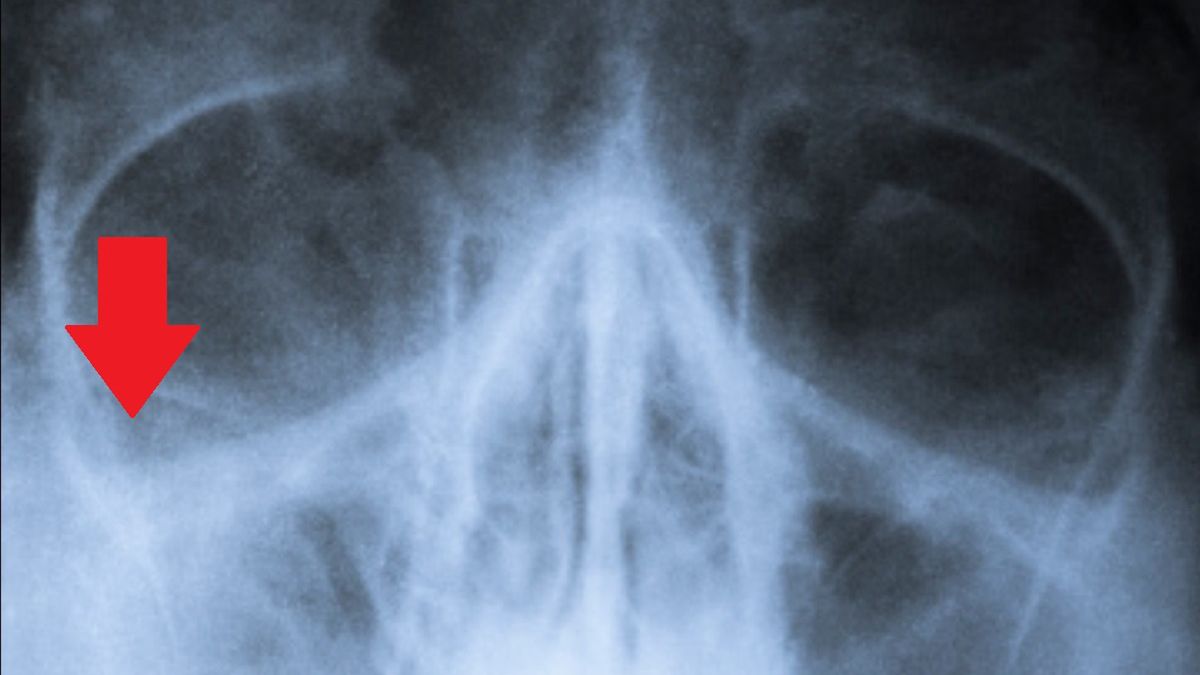

Jak podaje Science Alert, przewlekłe zapalenie błony śluzowej nosa czy zatok to problem aż 11 proc. Amerykanów. Z ostatnich ustaleń ekspertów wynika jednak, że podobny stan rzeczy może wynikać ze zmian w aktywności mózgu.

Zatkany nos, zapalenie zatok – przyczyny mogą okazać się zaskakujące